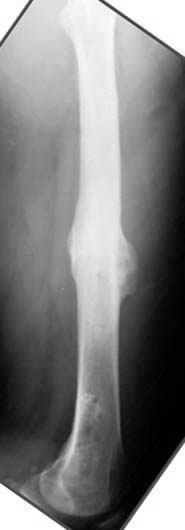

Несколько снимков из моей коллекции, чтобы разьяснить, почему мы до сих пор делаем различные варианты остеотомии.

На рисунке N1 предоперационный план лечения ложного сустава шейки бедра- линия ложного сустава, угол и направление введения импланта, клиновидная остеотомия в градусах и миллиметрах, второй снимок после коррекции, расчет, на сколько удлиняется конечность и размеры импланта;

N3 рисунок окончательный снимок, после операции моя рентгенограмма должен выглядеть примерно как эта картина. На N4 снимке клин перед удалением; N5 послеоперации 3 нед.; N6 окончательная рентгенограмма.

Отправитель: Evgueny Tschekashkin 24 Ноябрь 2004, 21:09

хотя даже если бы и инфекция , то nail exchange с рассверливанием канала - вариант дебрайдмента) Я думаю, что последовательность развития событий:

Узкий к-м канал - тонкий гвоздь- усталостный перелом дистальных винтов - развитие нестабильности и как ее результат остеолиз вокруг гвоздя - деформация анатомической оси бедра. Похоже, что я понял почему аппарат, а не новый гвоздь:-)